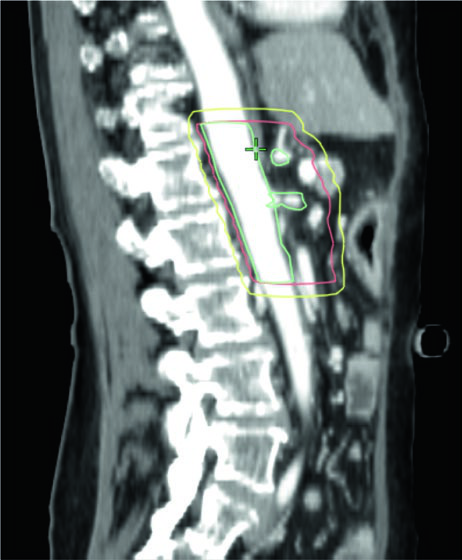

Volúmenes blanco en el escenario definitivo

| Volumen | Definición y descripción |

|---|---|

| GTV | Toda enfermedad macroscópica en imagen, incluyendo el tumor primario y la extensión vascular |

| ITV (opcional) | Si se utiliza enfoque ITV, delinear el GTV en todas las fases del 4D-CT |

| CTV alta dosis | Corresponde al GTV (o ITV si se utiliza) sin margen adicional |

| CTV dosis microscópica | Expansión uniforme ≥ 1 cm sobre toda la enfermedad macroscópica + cadenas CA y AMS + hilio esplénico (cuerpo/cola) + margen vascular adicional + porta hepatis opcional (cabeza) |

| PTV alta dosis | Expansión 0–0,5 cm, sustrayendo OARs críticos superpuestos con margen de seguridad: • 56 Gy/28 fx o 33 Gy/5 fx: sustraer estómago e intestino delgado sin margen adicional • 50 Gy/10 fx, 67,5 Gy/15 fx o 75 Gy/25 fx: sustraer con expansión de 0,5 cm (0,7 cm para interfaz larga) |

| PTV microscópico | Mínimo 0,5 cm; sin ITV en respiración libre, 1–1,5 cm craneocaudal |

Un detalle práctico que a menudo se subestima: dada la naturaleza infiltrativa del PDAC, el sobre-contorneo del GTV para incluir el parénquima pancreático circundante puede ser razonable, especialmente cuando se respalda con imagen diagnóstica adicional. En regiones de contacto directo entre GTV y OAR crítico, el PTV debe excluir el OAR con un margen de seguridad que exceda la expansión del PRV.